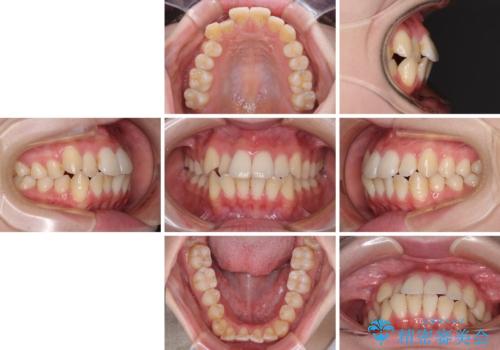

- 前歯の突出感とクロスバイトが気になり、インビザラインによる矯正治療を希望して来院された患者様です。

上顎側切歯(上の真ん中から2番目の歯)が舌側転位している場合、インビザラインでは仕上げきれないことが多く、更には無理して動かそうとすると歯髄壊死を起こすリスクが高いと言われています。

インビザラインで歯列を移動する前に、上顎前歯をワイヤー矯正で整え、その後上下歯列をインビザラインにて矯正治療を行うこととしました。